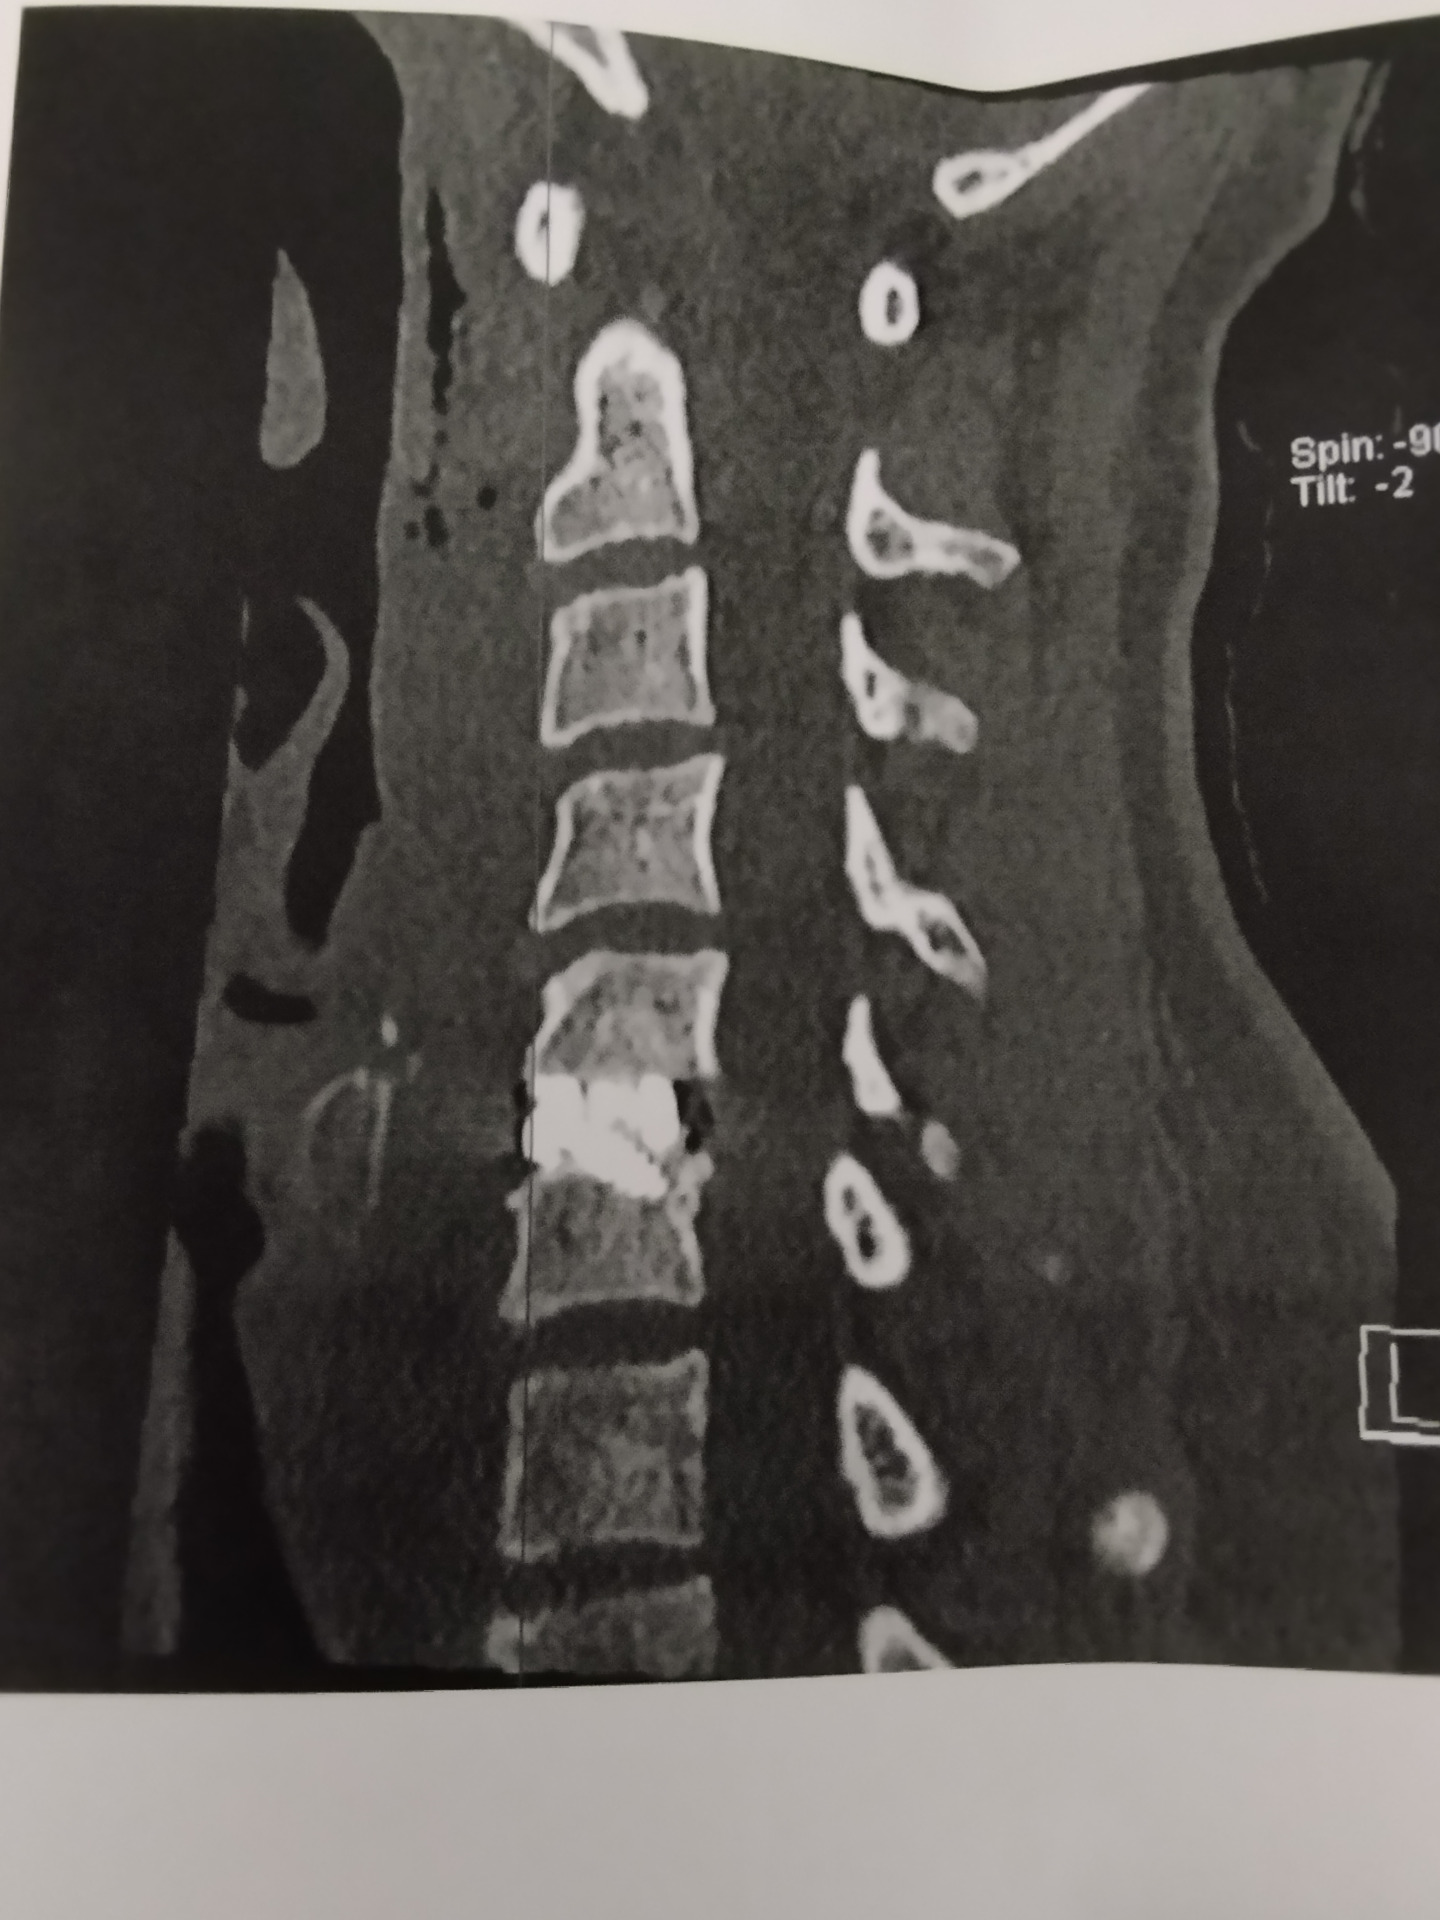

Nem volt, mert akkor, ott leblokkoltunk mindketten a férjemmel. Igaz, hogy 8 évvel ezelőtt is mondták, hogy majd meg kell műteni, de egyáltalán nem tűnt égetőnek, hiszen 1 év táppénz után visszaküldtek dolgozni könnyített munkakörbe. (Ez az, amit nem talál egy idegen külföldön.) Még adott 3 beutalót az idegsebész olyan vizsgálatokra, amiket a műtét előtt kellett elvégezni a következő 2 hétben, az ünnepek alatt. December 27-én mentem kontrollra a röggel a fejemben, 29-én pedig még egy EMG vizsgálatra, konzultációra az altató orvossal és egy friss vérvételre. Január 3-án CT-re vitt a férjem, ahol azt nézték, hogy a nyaki csigolyáim mennyire vannak lemeszesedve.

Kora délután jött a doktornő vizitelni, elmondta, hogy minden jól ment. Nagyon meg kellett faragnia a csigolyákat, mert jól le voltak meszesedve, ezért kicsit elhúzódott a műtétre tervezett idő. Kaptam egy gyógyászati segédeszköz ügynöktől egy méretre szabott nyakmerevítőt és este a vacsorához már felülhettem az ágyon.